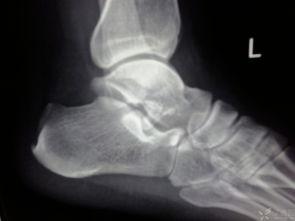

距骨,听起来是不是有点陌生?其实,它就是脚踝骨中那个小小的、形状像豆子的那块骨头。别小看了它,它可是支撑你行走的重要部分。一旦距骨骨折,那可就麻烦了,不仅疼痛难忍,连日常活动都可能受到影响。